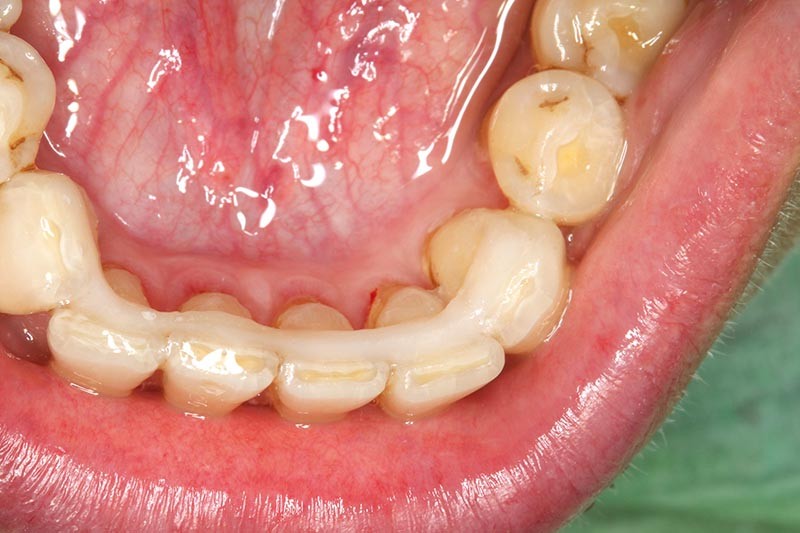

Une patiente présente un proglissement mandibulaire aboutissant à une inversion d’occlusion au niveau des incisives (fig. 2).

Au-delà du préjudice esthétique, il induit des forces importantes en direction vestibulaire sur les incisives mandibulaires. Ces incisives présentent une légère mobilité. La radio rétro-alvéolaire montre un élargissement desmodontal et une perte osseuse verticale sans cratérisation ni inflammation (fig. 3).